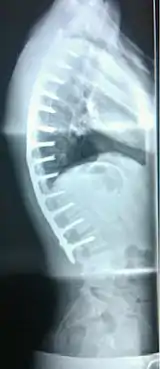

| Scheuermann's disease | |

| Other names | Scheuermann's kyphosis, Calvé disease, idiopathic juvenile kyphosis of the spine |

| Scheuermann's disease on lateral Xray of the T spine | |

Scheuermann's disease is a self-limiting skeletal disorder of childhood. Scheuermann's disease describes a condition where the vertebrae grow unevenly with respect to the sagittal plane; that is, the posterior angle is often greater than the anterior. This uneven growth results in the signature "wedging" shape of the vertebrae, causing kyphosis. It is named after Danish surgeon Holger Scheuermann.[3][4][5]

Diagnosis is typically by medical imaging. The degree of kyphosis can be measured by Cobb's angle and sagittal balance.